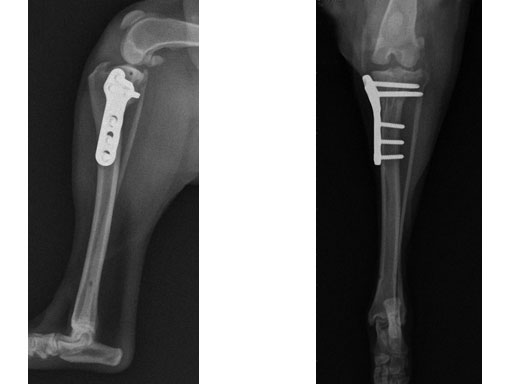

Case 3: Eight-year-old Australian cattle dog

(Case provided by Brian Beale, Houston, USA)

An 8-year-old, female, spayed, 24 kg Australian cattle dog. This breed has short stocky legs and is very energetic and strong. The added strength of the 3.5 mm plate over the TPLO 2.7 mm plate was an advantage. The smaller head profile and shorter length of the TPLO 3.5 mm small stature plate allowed it to fit nicely on this patient.